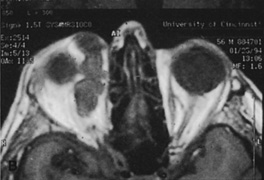

HISTORY AND PHYSICAL EXAMINATION A wide range of signs and symptoms may alert the ophthalmologist to involvement of the orbit by a pathologic process. These include proptosis or globe displacement; compressive optic neuropathy with visual field or visual acuity loss; refractive changes such as progressive hyperopia, restricted eye movements, and diplopia; optic disc changes, including pallor or edema; and fundus changes such as choroidal folds. These manifestations may be the consequences of a primary intraorbital disease or may occur secondary to involvement of the orbit by a process extending from the overlying soft tissues, periorbital sinuses, or intracranial cavity. All patients with suspected orbital pathology should have a thorough ophthalmic history and physical examination. Detailed questioning about the nature, onset, and progression of the chief complaint is necessary to formulate a differential diagnosis. Previous ocular and general medical history related to diseases, operations, medications, and family history should be obtained. A general review of systems will identify risk factors for related systemic diseases, such as hyperthyroidism, metastatic cancer, or lymphoma. A complete examination of the eye and periocular tissues is essential. Abnormal protrusion or displacement of the globe, extraocular motility disturbances, soft-tissue changes, and decreased corneal or periorbital cutaneous sensation should be specifically sought. Special attention always should be directed to evaluation of optic nerve function. Visual acuity testing alone is not sufficient because visual acuity often is preserved initially in patients with compressive optic neuropathy. All patients should be examined closely for detection of an afferent pupillary defect, abnormal color vision, or loss of contrast sensitivity. Formal perimetry should be performed to rule out peripheral field loss. If the presentation has been gradual, evaluation of old photographs may help establish the time course of the pathologic process. In selected cases, appropriate blood work to help identify orbital inflammatory or neoplastic processes also should be obtained. ORBITAL IMAGING Valuable information about the nature and extent of an orbital pathologic process is provided by imaging studies such as computed tomography (CT) scan, magnetic resonance imaging (MRI), and orbital echography. Better spatial resolution, ready accessibility, and lower cost make CT the preferred choice for orbital imaging in most cases. Orbital fat provides a natural contrast between most adjacent orbital structures on CT scanning, and orbital bones are visualized well. Computed tomography is essential for evaluation of the orbital bones because they cannot be imaged with MRI. Direct coronal or sagittal images are important to identify the relationship of a lesion to the optic nerve so that the surgical approach can be planned to avoid traversing the optic nerve (Fig. 1). Newer multislice helical CT scanners allow continuous acquisition of data so that a single rapid pass allows formatting in axial, coronal, and sagittal planes. Multislice CT provides shorter examination times with reduced motion artifact and radiation exposure when compared with conventional CT. Magnetic resonance imaging is useful in selected cases, especially when evaluating the orbital cranial junction. Significant bony artifact and a lack of orbital fat in the orbital apex make CT scan resolution of the orbital apex structures poor. Because cortical bone has low signal on MRI, there is no bone artifact when viewing the orbital apex on MRI. The lack of intervening fat in the apex to provide contrast is overcome on MRI because contrast is provided by the individual nuclear characteristics of each tissue so that the orbital apex structures are visualized well. Consequently, conditions that affect the optic nerve and chiasm, such as optic nerve meningioma and glioma, generally are evaluated with MRI rather than CT scan (Fig. 2). Use of a contrast agent such as gadolinium can further enhance the T1 signal intensity of lesions and is particularly helpful in imaging areas where there has been a breakdown in the blood–brain barrier. Because orbital fat produces a bright signal on T1-weighted images, orbital MR usually is performed with “fat suppression” to prevent masking of lesions. However, incomplete fat suppression can produce artifacts that may be misinterpreted as abnormal enhancement. A few other orbital conditions are better visualized with MRI than CT scanning.1–3 Often, organic foreign bodies, such as wood, are not imaged well with CT scan. These foreign bodies often are visible with MRI. However, care must be taken when imaging any metallic intraocular or intraorbital foreign body because the strong magnetic field of the MR scanner may cause the foreign body to shift position and damage surrounding structures. In some tumors and vascular anomalies, high blood flow is appreciated on MRI. This is caused by a lack of signal, known as a flow void, created by blood flowing rapidly through larger vessels. Tumors that originate in the brain and extend into the orbit secondarily, such as sphenoid wing meningioma, also are visualized well with MRI. However, bony detail and calcification within the meningioma are not imaged well. In unusual circumstances such as this, CT scan and MRI may prove to be complementary, and both techniques may be required to fully evaluate the orbital disease process. Orbital echography can provide useful information in the evaluation of orbital disorders. Because each tissue has its own acoustic characteristics, echography can provide a high degree of tissue contrast. Spatial resolution also is quite good. In some situations, echography can provide information not available on CT scan or MRI. These instances include detection and measurement of blood flow4 and intraoperative localization of small foreign bodies.5 Orbital echography requires specialized equipment and a large amount of expertise to obtain the detailed information that is readily available with CT scan or MRI; consequently, its use has decreased. Recent advances in orbital imaging have been summarized by Lee and colleagues.6 |